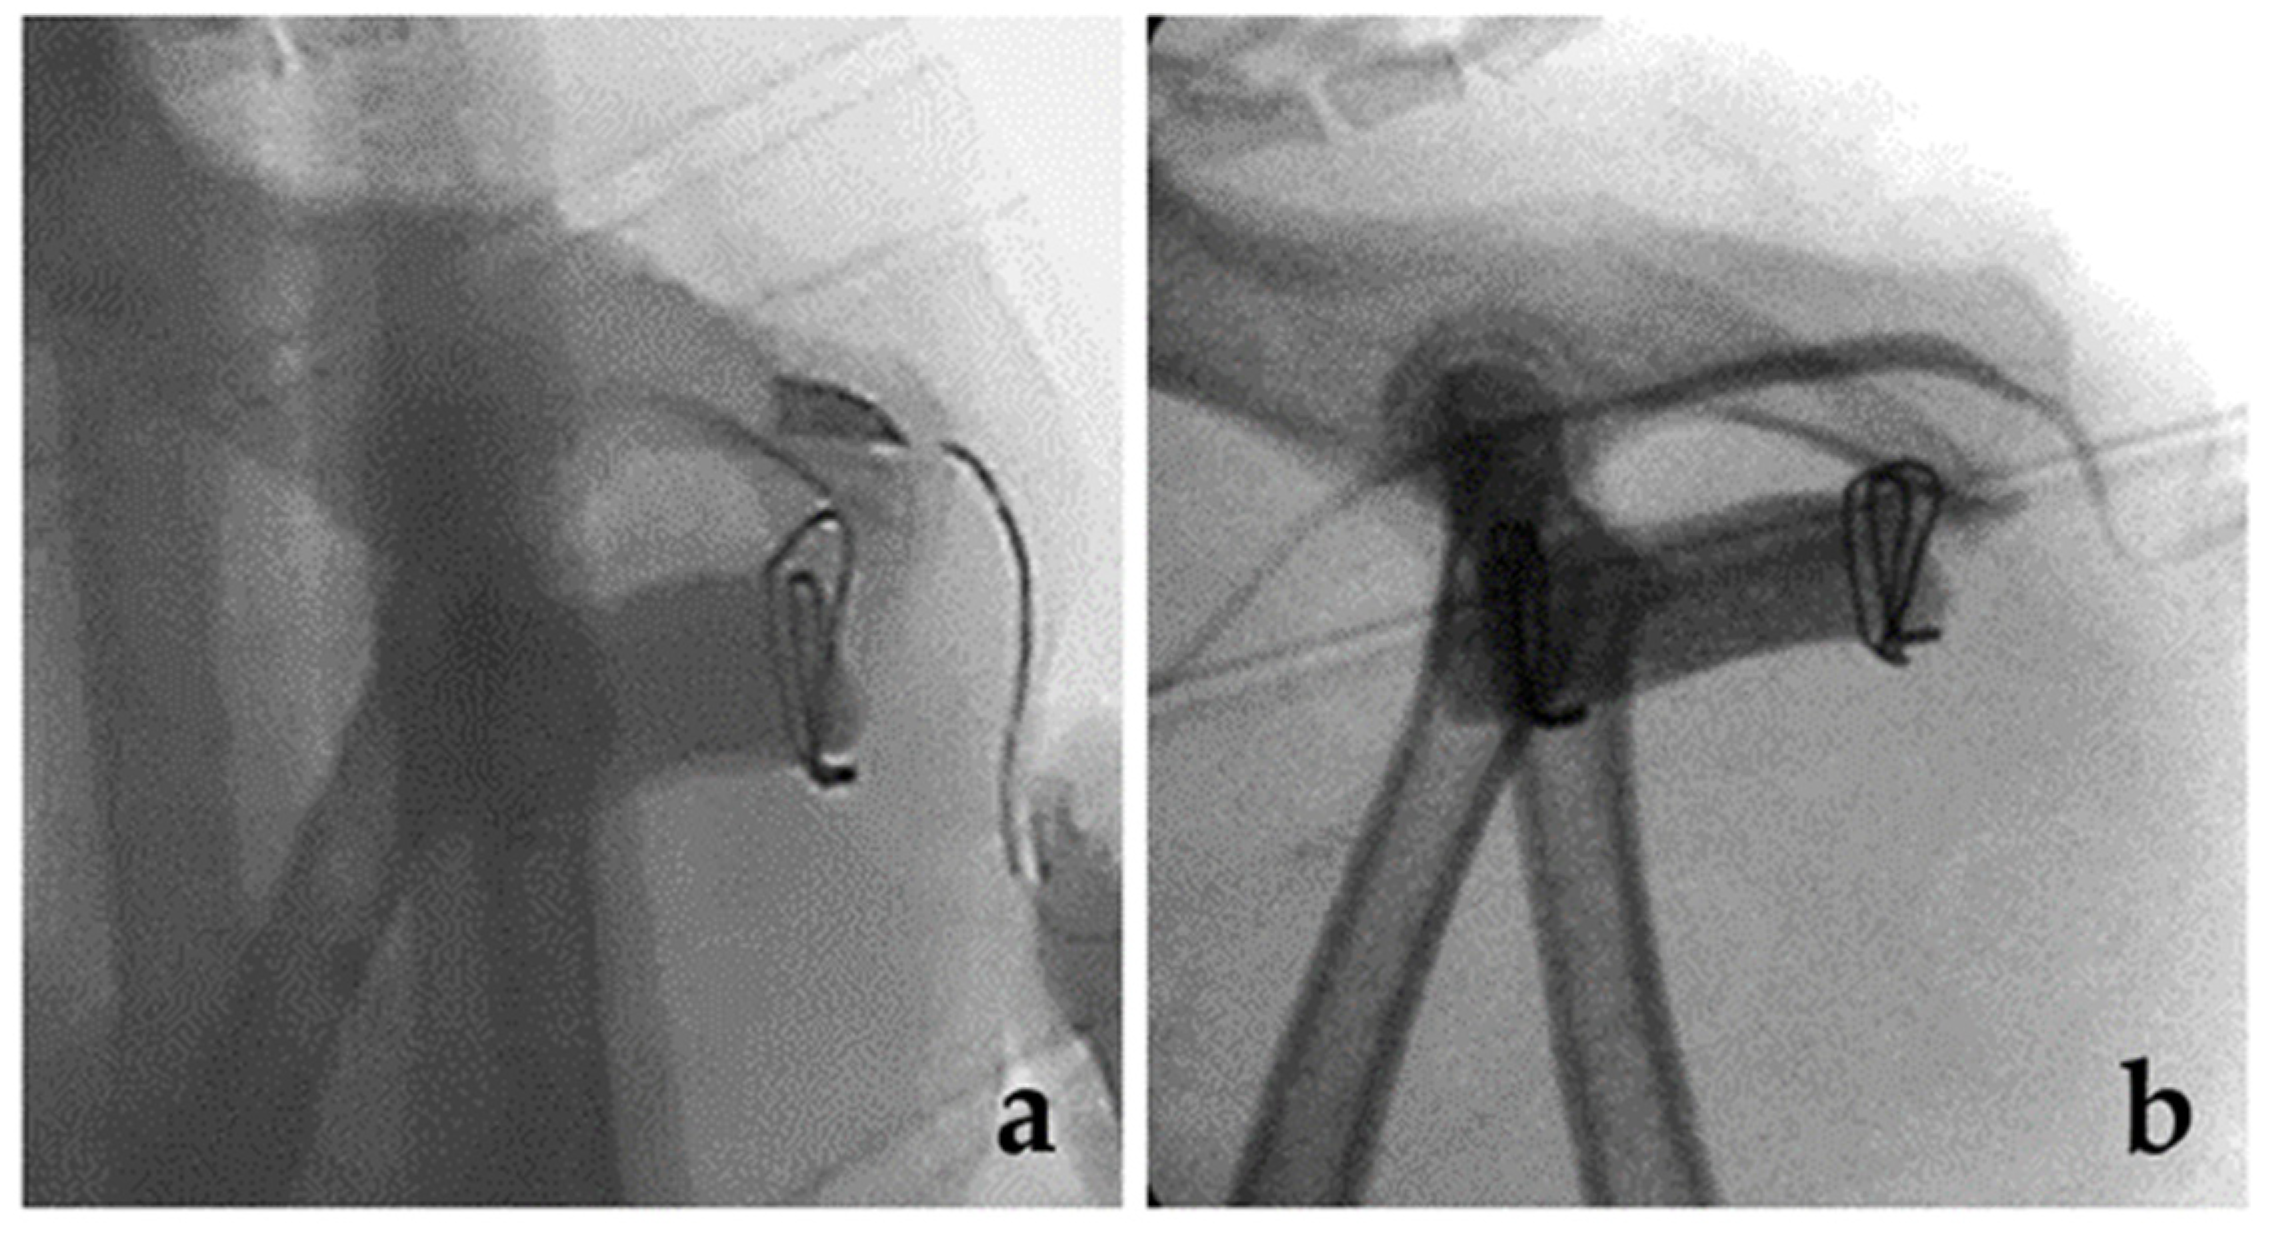

2.3. Complication and IM Release